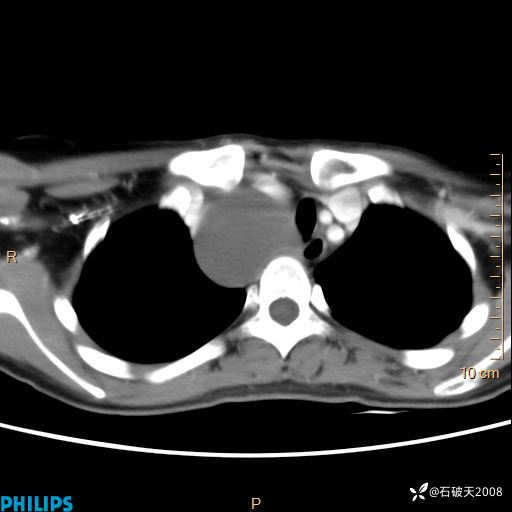

影像诊断要密切结合临床,真的很有必要(病理已公布)

女 21岁 主 诉:发现右侧颈部肿物18年余。

现病史:18年余前患者无明显诱因发现颈部偏右侧有一肿物,具体大小不明确,咳嗽、憋气时肿物增大,局部无疼痛,无吞咽不适,无胸闷及呼吸困难,至当地医院检查考虑良性病变(具体不详)并未做特殊处理,现患者自觉肿物随年龄增长而进一步变大,今日至我院行颈部CT平扫+增强提示:1.右侧颈根部、锁骨上窝及纵隔内异常密度影,考虑良性病变,淋巴管瘤?囊肿?请结合临床。2.双侧颈部小淋巴结。建议结合临床及其他相关检查。现为行进一步治疗,门诊以“颈部局部肿物”为诊断收住我科,发病来患者神志清,精神可,饮食睡眠可,大小便正常,体重无下降。

冠状位